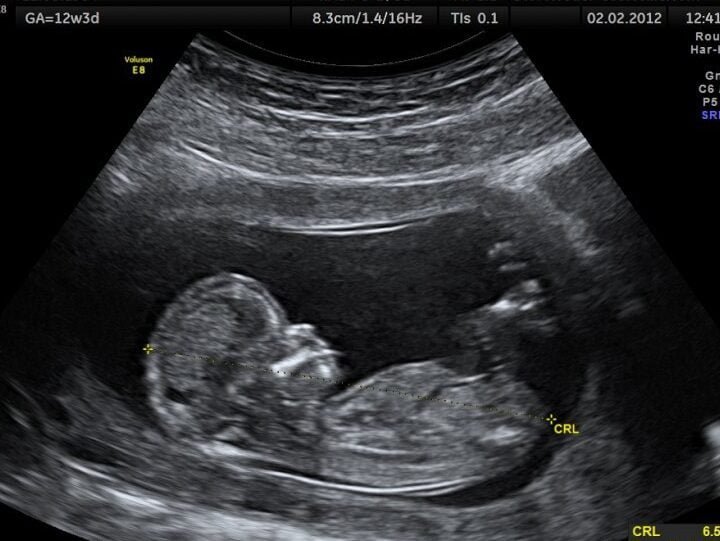

La ecografía es un método de diagnóstico no invasivo que utiliza ondas sonoras para producir imágenes del interior del cuerpo. Esta técnica es fundamental para detectar y diagnosticar various patologías, como problemas cardiacos, hepáticos, renales, entre otros.

La ecografía es un tipo de examen médico no invasivo que utiliza ondas sonoras de alta frecuencia para producir imágenes del interior del cuerpo. En las clínicas de Argentina, la ecografía se utiliza para diagnosticar y monitorear una variedad de condiciones médicas, como el crecimiento fetal durante el embarazo, lesiones en los tejidos blandos, problemas en los órganos abdominales, como el hígado o los riñones, y enfermedades vasculares. La ecografía es una herramienta valiosa para los médicos, ya que les permite evaluar el estado de salud de los pacientes de manera segura y no invasiva.

En las clínicas de Argentina, se realizan various tipos de ecografías, cada una diseñada para evaluar áreas específicas del cuerpo. Algunos de los tipos más comunes de ecografías son la ecografía abdominal, que evalúa los órganos abdominales, como el hígado, el bazo y los riñones; la ecografía pélvica, que evalúa la pelvis y los órganos reproductivos; la ecografía obstétrica, que monitorea el crecimiento fetal durante el embarazo; y la ecografía vascular, que evalúa el flujo sanguíneo en las arterias y venas. Además, algunas clínicas también ofrecen ecografías especializadas, como la ecografía de mama o la ecografía de tiroides. Cada tipo de ecografía requiere habilidades y conocimientos específicos, por lo que es importante elegir una clínica que tenga experiencia en el tipo de ecografía que se necesita.